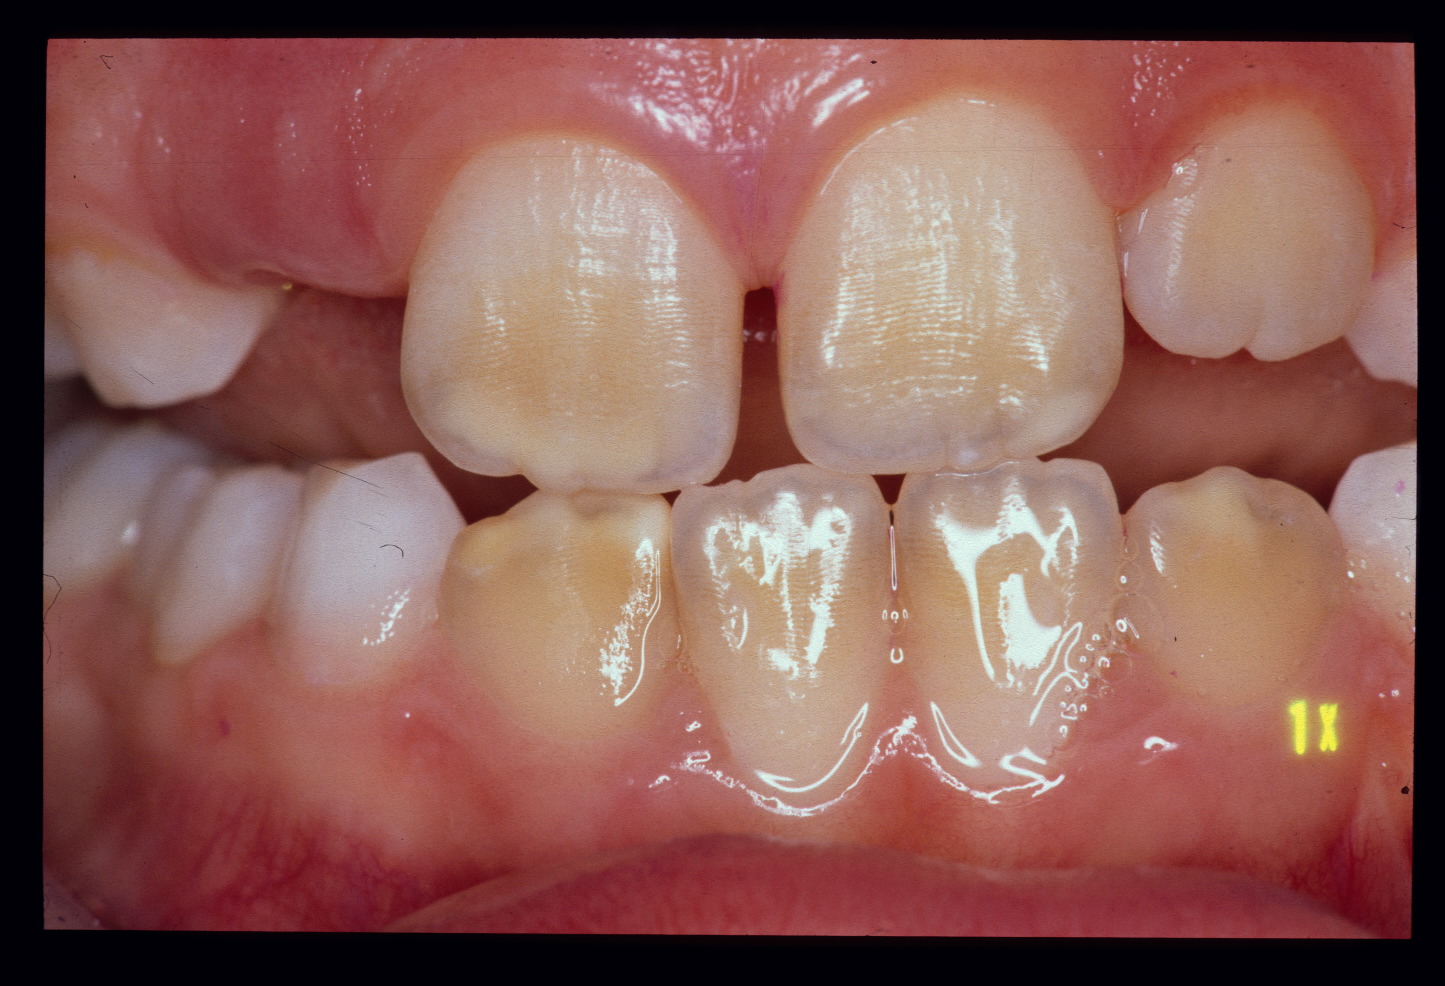

На фотографии зубы с нарушением эмали из-за недостаточного развития ее поверхностного слоя – гипоплазия.

Кариес в виде пятна следует отличать от таких заболеваний, как гипоплазия эмали и флюороз.